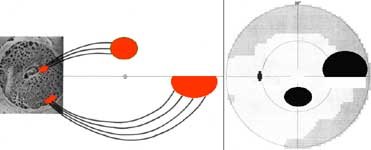

Mincler ve svých experimentech s křenovou peroxidázou injikovanou do terče zrakového nervu opic zjistil, že při aplikaci blízko okraje terče tato látka pronikne do okrsku gangliových buněk temporálně od makuly a nepřekročí horizontální čáru. V zorném poli tomuto okrsku odpovídá nasální skok v protilehlé polovině zorného pole. Při aplikaci nad střed terče tato látka pronikne do okrsku gangliových buněk v horní části makulární oblasti a v zorném poli tomu odpovídá paracentrální skotom v protilehlé polovině zorného pole.